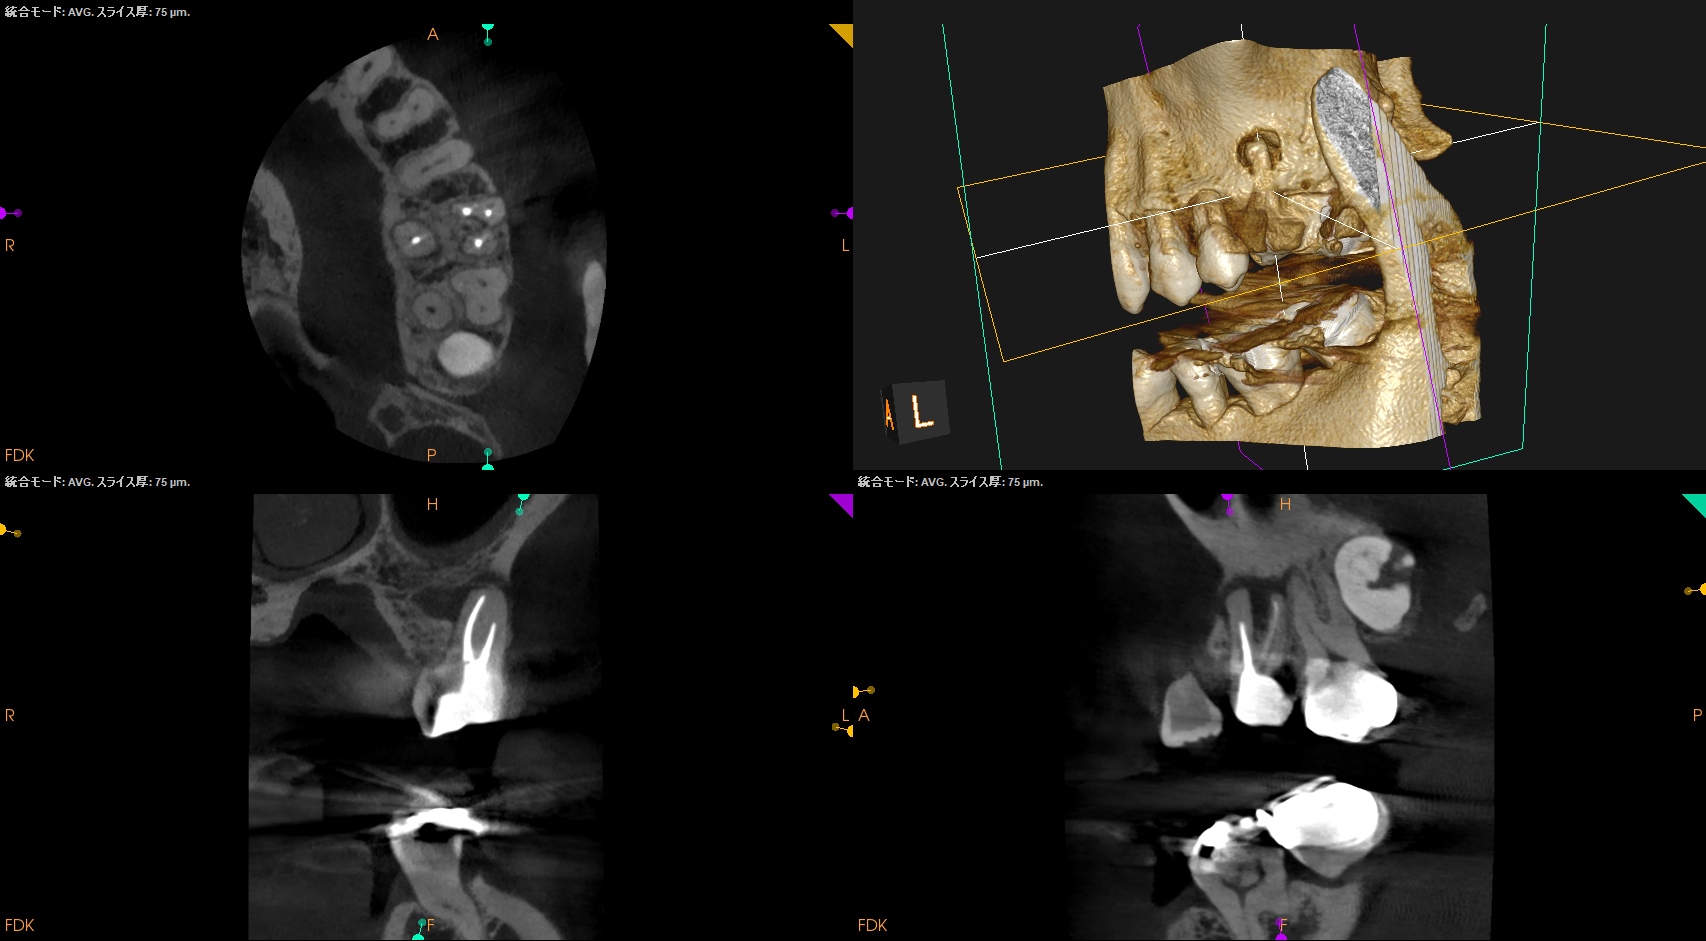

Pre-op Endo Test(2026.1.28)

MB1

MB2

DB

P

Selectiveに再根管治療をするとすれば、

MB1もしくはMB2

MB1とMB2

は穿通させる必要性があるだろう。

が、

Pはその必要があまりないだろう

ということがわかる。

MB2を発見・穿通させる必要があるかどうか?はこのように術前にCBCTを正しく分析すれば予想ができる。